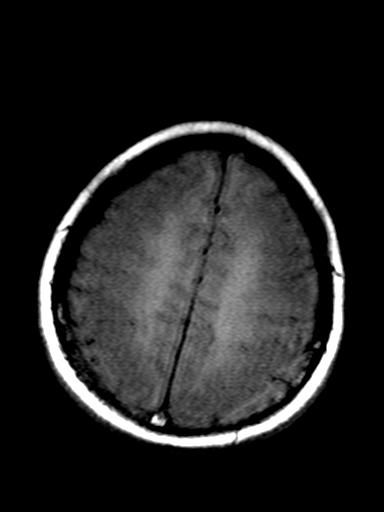

发热、头痛伴精神异常1周

较对称性脑白质异常信号,深部白质t2明显低信号(铁质沉积过多?)

考虑脑白质病变,请结合临床病史及实验室检查进一步分析。

f 23岁